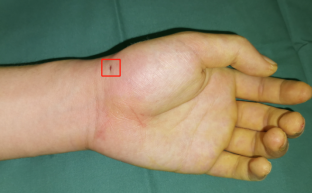

唐医生使用天玑骨科机器人辅助手术,精准定位,避免反复穿刺导致的二次损伤,大大缩短手术时间,术后促进骨质愈合,仅手腕处一个钉眼大小的伤口。

术后照片